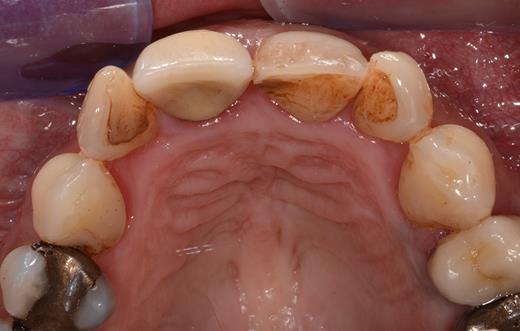

Clinical examination revealed two small mucosal openings on either side of the incisive papilla, which could be probed partially (Fig. 1). Palpation of this area was painful. Two gutta-percha points were inserted into the two openings (Fig. 2). The cone beam computed tomography (CT) confirmed two patent NDPs with oronasal communication (Fig. 3).

Preoperative clinical situation: occlusal view of the maxillary arch presenting two small depressions of the mucosa on either side of the incisive papilla (blue arrows).

Occlusal view of the maxillary arch presenting two small openings of the mucosa with two inserted gutta-percha points on either side of the incisive papilla.